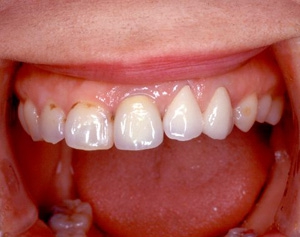

インセラム(オールセラミック)症例②

治療前治療前術前 治療後治療後術後 歯の尖端の透明感までよく再現できている。